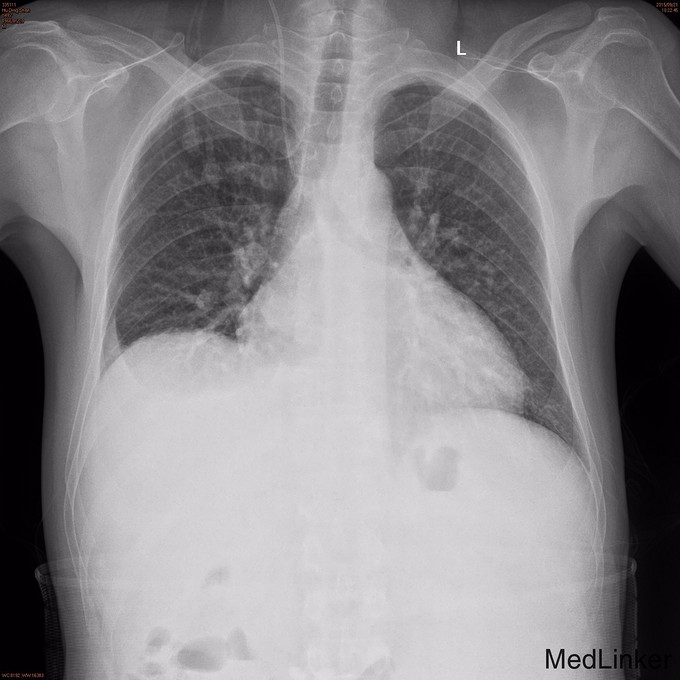

查体:全身皮肤有黄染,见肝掌及蜘蛛痣,腹肌软,腹部可见陈旧性手术疤痕,移动性浊音阴性,肠鸣音正常。 辅查: 腹部MRI:1.肝硬化,脾大,少量腹水,食道下段、胃底及脾门周围静脉曲张。 2.肝内胆管、左肝管扩张,门脉淋巴水肿;腹膜后、心膈角区多发肿大淋巴结,请结合临床。 3.胆囊术后缺如。 4.胰腺体尾部未见显示。

诊断:1.胆汁性肝硬化,2.胆肠吻合术后 治疗:入院后完善检查在全麻下行肝移植术,术程顺利,术后恢复良好,术后切口感染,于拆线后重新缝合.患者无诉不适,腹软、无压痛。剑突下切口尚未拆线,有少量渗液,无红肿。予抗排斥治疗,定期复查。